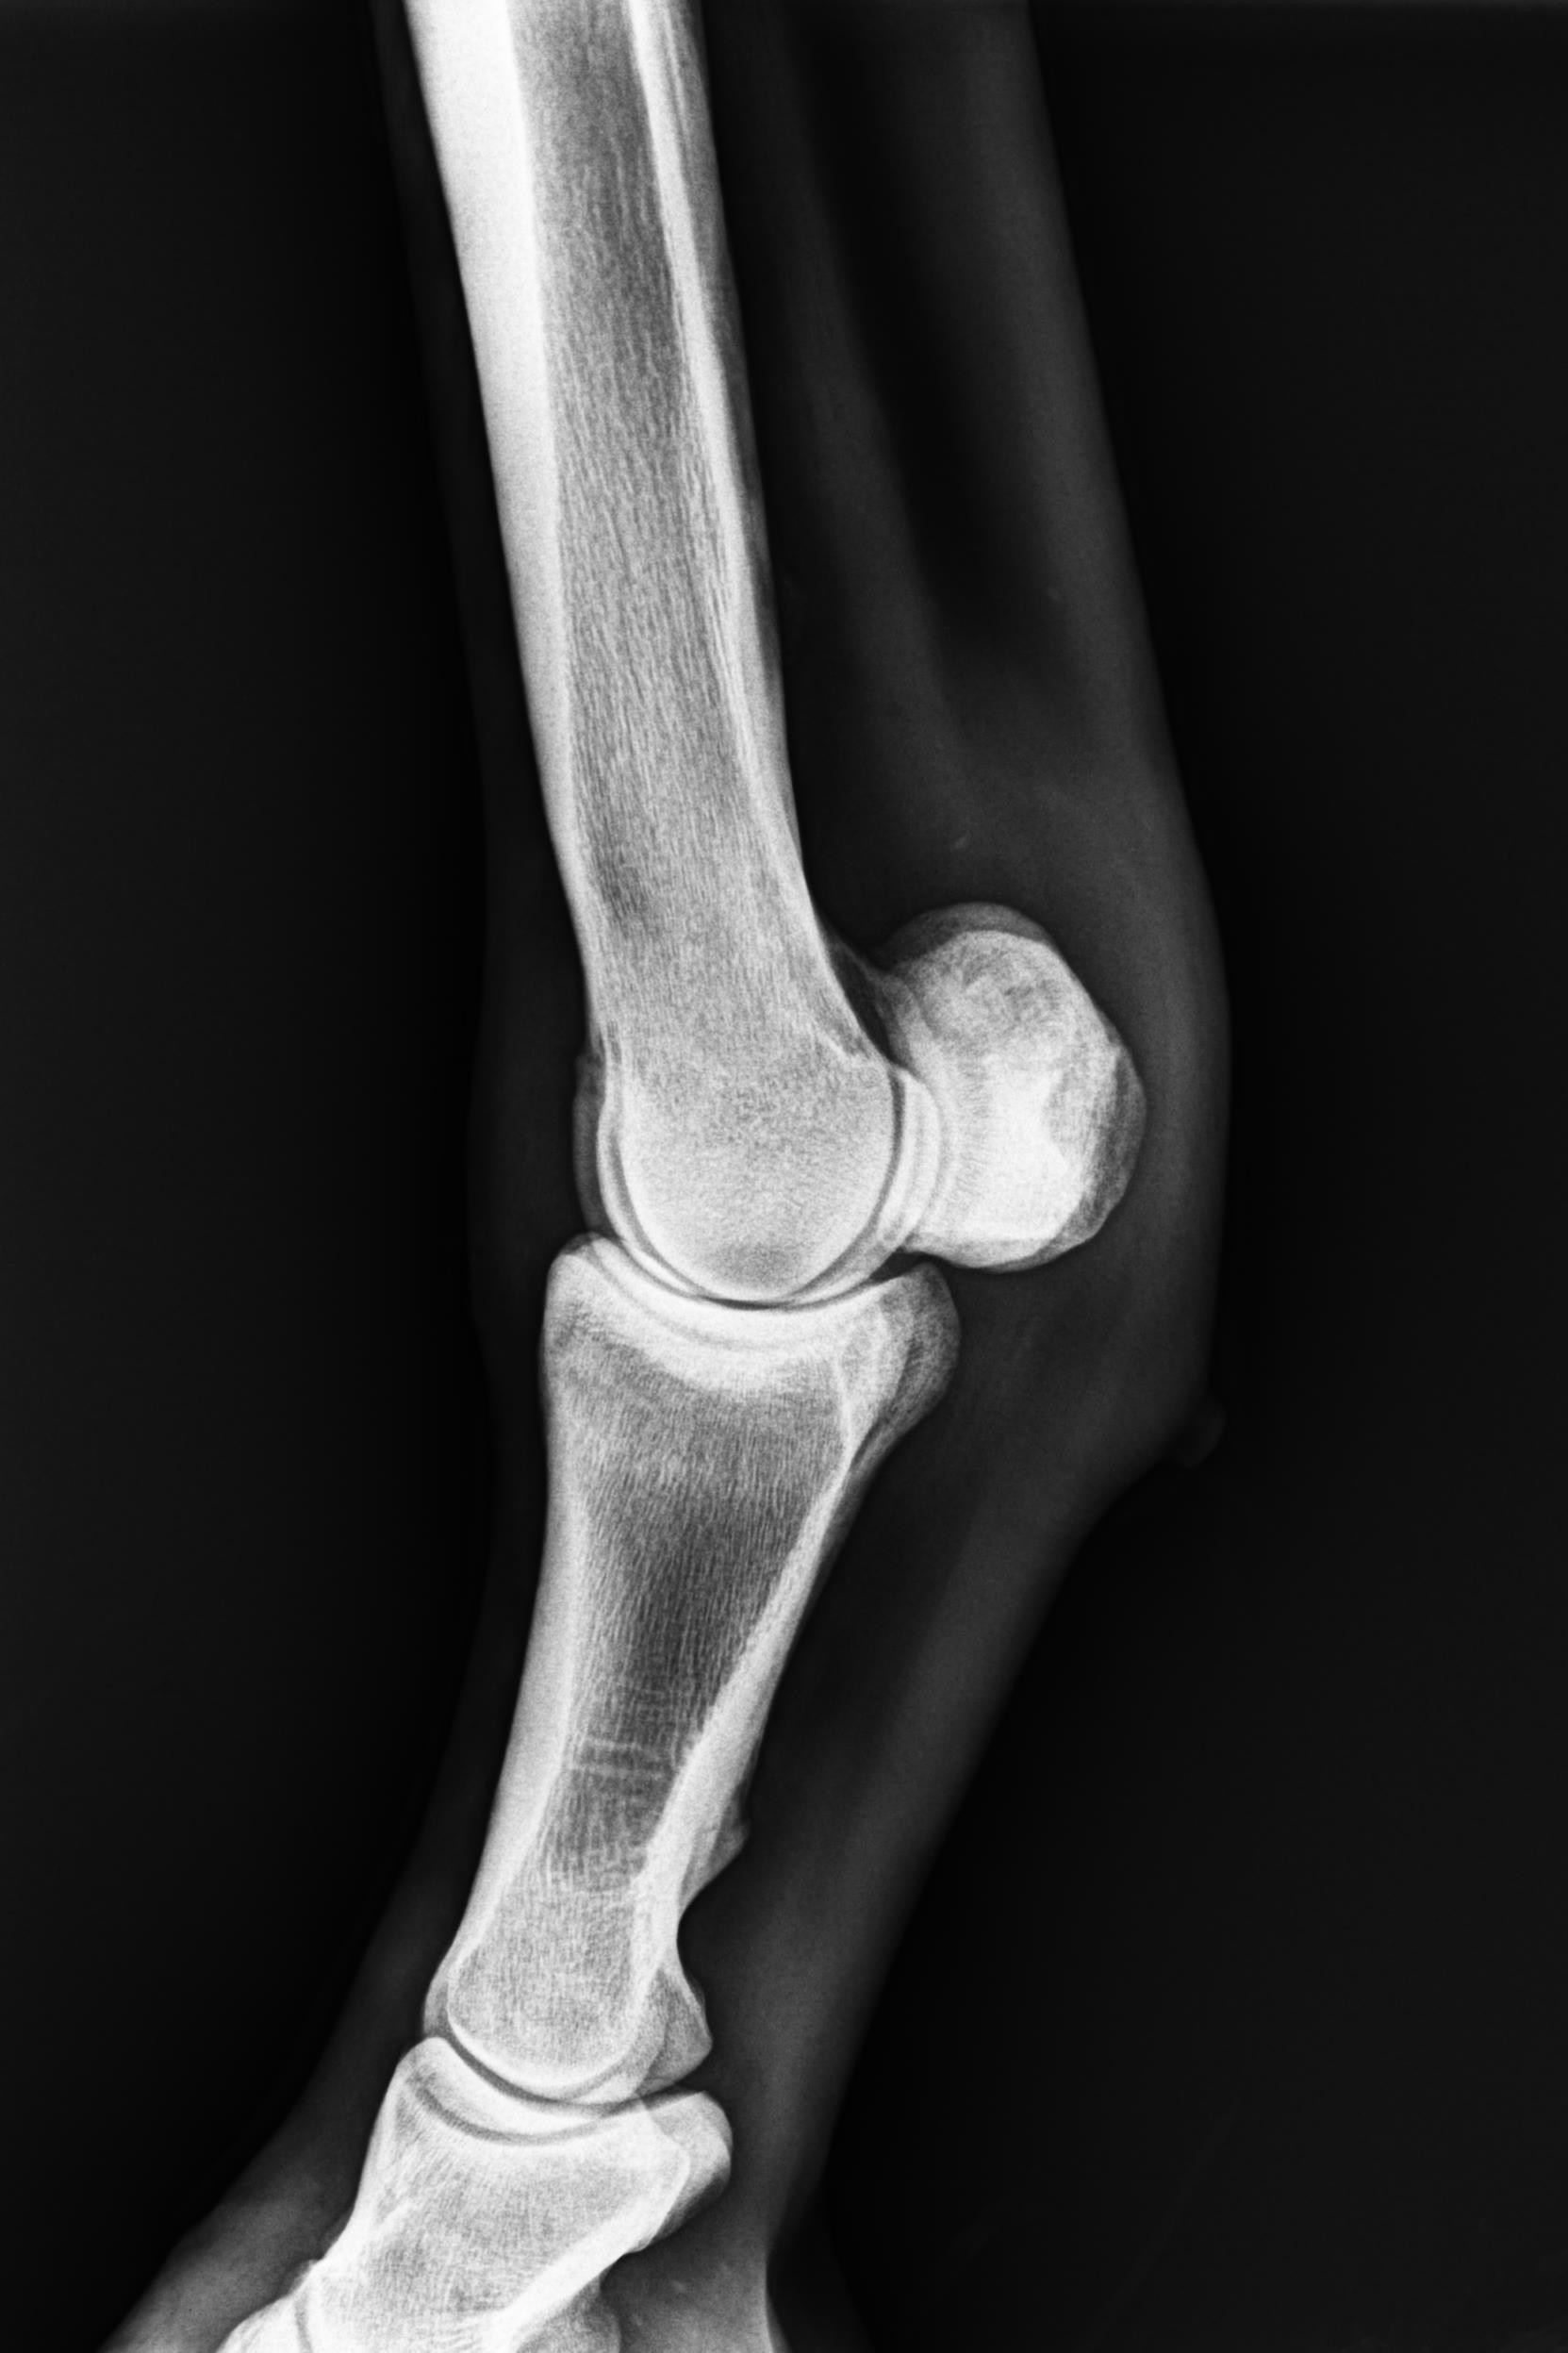

そんな状況の中、1月9日にレントゲン検査を受けると「左前肢外側の種子骨のボーンシスト」が原因と判明しましたので、サラブレッドオークションへ出品とさせていただきます。現状のままでは競走馬としてのデビューは難しいかも知れません。皆様には現状をご理解いただき、事前に獣医検査を受ける等、ご納得をいただいた上でのご検討、ご入札をお願いし、現状渡しのノークレーム、ノーリターンでお願いいたします。

セールの後からお預かりして来ましたが、レントゲン検査を受けて獣医から「このまま調教を進めたら骨折するリスクが大きい」との所見でした。競走馬は勿論ですが、現状のままでは乗馬としても厳しいと思います。(Team百馬力・原翼氏)